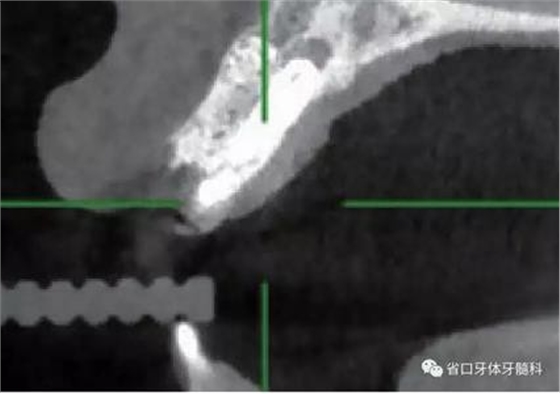

(1)微創(chuàng)拔牙及即刻種植:術(shù)前拍攝口內(nèi)照及實(shí)施牙周基礎(chǔ)治療。常 規(guī)消毒鋪巾阿替卡因局麻下微創(chuàng)拔除上頜右側(cè)中切牙,搔刮拔牙窩及根尖肉 芽組織。探測牙槽骨唇側(cè)骨壁及鄰面牙槽嵴完整,牙齦無撕裂。不翻瓣下于上頜右側(cè)中切牙缺隙近遠(yuǎn)中中點(diǎn)的腭側(cè)牙槽骨及根方定位,按照逐級預(yù)備的原則,緊貼牙槽窩腭側(cè)骨壁制備種植窩洞,植入Zimer®3.7mm×13mm TSV種植體1顆,植入扭矩>35N·cm,以O(shè)sstell測量種植體的ISQ值為68。 種植體平臺位于唇側(cè)齦緣中點(diǎn)下3mm,與唇側(cè)骨壁內(nèi)側(cè)面形成的跳躍間 隙約2mm,置入Bio-Oss®細(xì)顆粒骨粉0.25g,上愈合基臺關(guān)閉創(chuàng)口。術(shù)后 CBCT檢查顯示:種植體利用牙槽窩根方骨質(zhì)固位,緊貼牙槽窩腭側(cè)骨壁, 其唇側(cè)面與牙槽窩唇側(cè)骨壁的內(nèi)側(cè)面所形成的跳躍間隙(約2mm)可見顆 粒狀顯影物充填。牙槽窩的唇側(cè)骨壁及唇側(cè)倒凹無缺損穿孔。

圖19 術(shù)后MCT